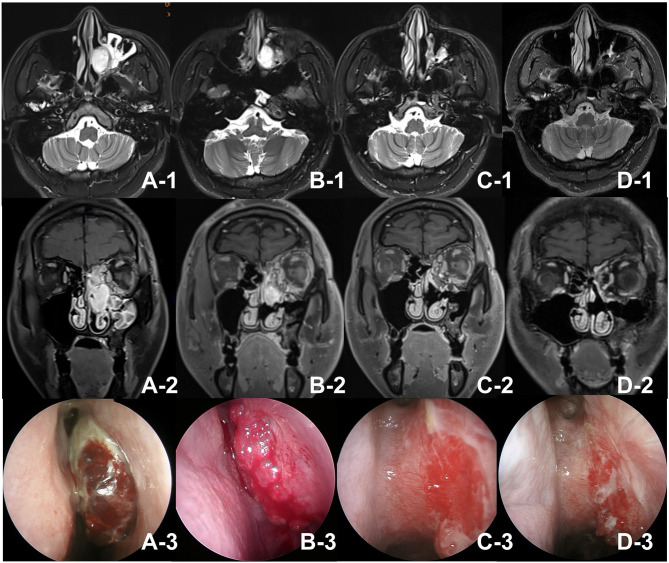

在本病例报告中,我们描述了一名左眼窝和鼻腔血管瘤反复发作的 21 岁男子。传统的手术并不成功,因此我们使用了贝伐单抗,一种抑制血管生长的药物。这种方法大大缩小了肿瘤的体积,并止住了频繁的鼻出血。两年多来,肿瘤一直得到控制,没有出现大的副作用,这表明贝伐单抗是治疗复发性血管瘤的一种很有前途的非手术疗法。

In this case report, we describe a 21-year-old man with recurrent hemangiomas in his left eye socket and nasal cavity. Traditional surgeries were unsuccessful, so we used Bevacizumab, a drug that inhibits blood vessel growth. This approach significantly reduced the tumor size and stopped frequent nosebleeds. Over two years, the tumor remained controlled without major side effects, suggesting Bevacizumab as a promising non-surgical treatment for recurrent hemangiomas.